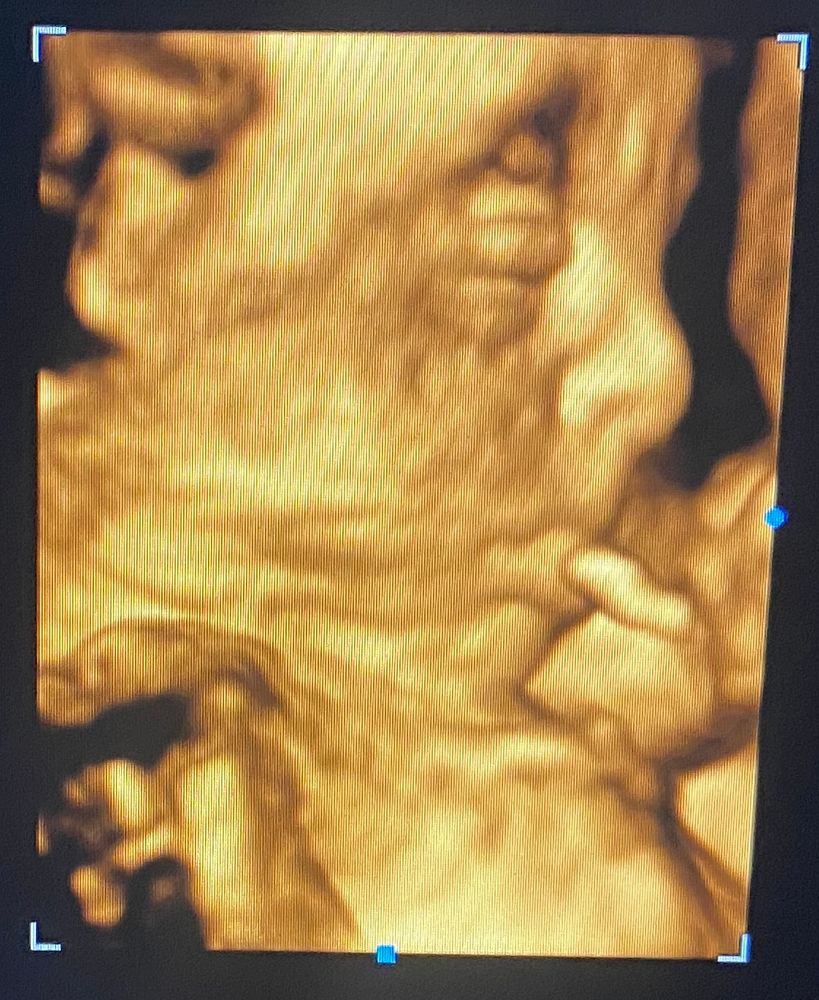

Маловесный плод 31н Первое узи